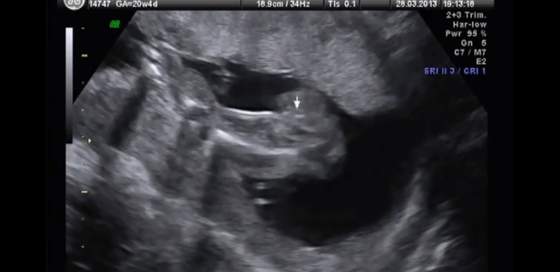

poniżej zdjęcie 20w4d

po prawej to pupa, po lewej takie dwie jasne to kości udowe, a to co pokazane jest kursorem, to wg doktora ziarno kawy